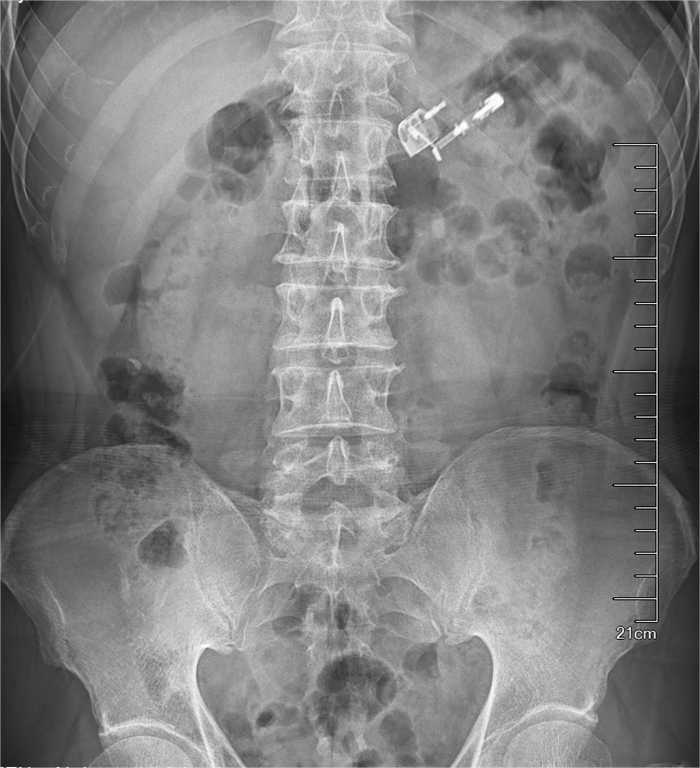

4月中旬,拉薩公安打掉一個扒竊犯罪團(tuán)伙,其中一名嫌疑人為逃避法律打擊吞下一個打火機(jī),公安看守人員發(fā)現(xiàn)異常情況后緊急與西藏阜康醫(yī)院取得聯(lián)系,并把嫌疑人送到醫(yī)院救治。經(jīng)門診急查腹部平片顯示打火機(jī)位于胃腔內(nèi)。消化內(nèi)科醫(yī)生沈燕如、麻醉醫(yī)生鄧富強(qiáng)、護(hù)師白央、護(hù)工白瑪倉決為嫌疑人進(jìn)行急診胃鏡下取異物治療。